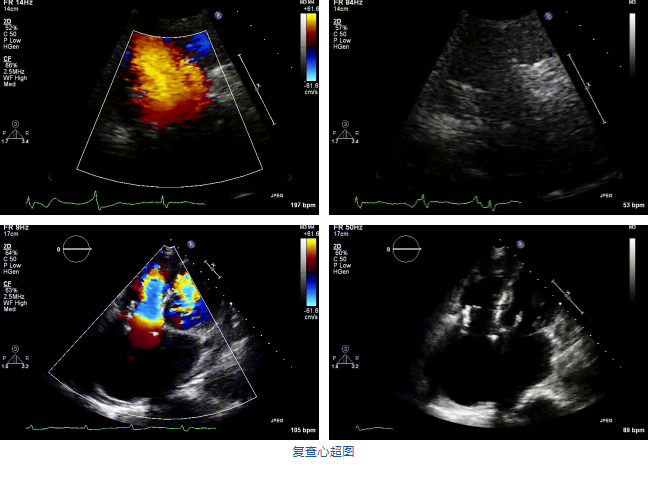

結(jié)合術(shù)前CT評估結(jié)果,葛均波院士團(tuán)隊最終決定選用LuX-Valve Plus 50mm和55mm兩種型號的瓣膜,并于2021年11月30日順利完成LuX-Valve Plus經(jīng)血管三尖瓣置換術(shù),手術(shù)室即刻拔除氣管插管,術(shù)后第二天轉(zhuǎn)出心內(nèi)科監(jiān)護(hù)室,下床活動。術(shù)后患者三尖瓣反流癥狀得到顯著改善,復(fù)查心超結(jié)果顯示人工三尖瓣瓣膜支架固定穩(wěn)定,瓣葉關(guān)閉形態(tài)未見異常,未見明顯反流。